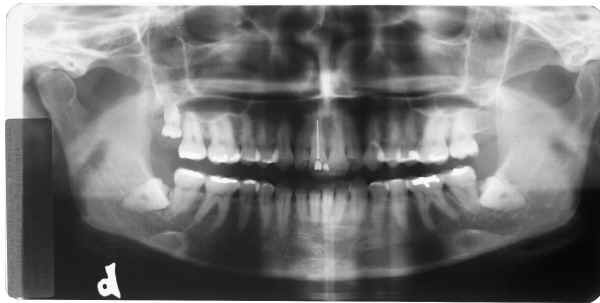

RX superior esquerdo

início

Rx superior direito

Rx inferior esquerdo

Rx inferior direito

Qual destes lados não foi editado?

Responda, justificando, e receba a resposta com as fotos originais!

Matematicamente a probabilidade de erro na 1ª resposta é igual a 75% = 3/4 x 100

Matematicamente a probabilidade de erro na 2ª resposta é igual a 50% = 1/2 x 100

Não aposte sua prova jurídica nisto, responda e verás!